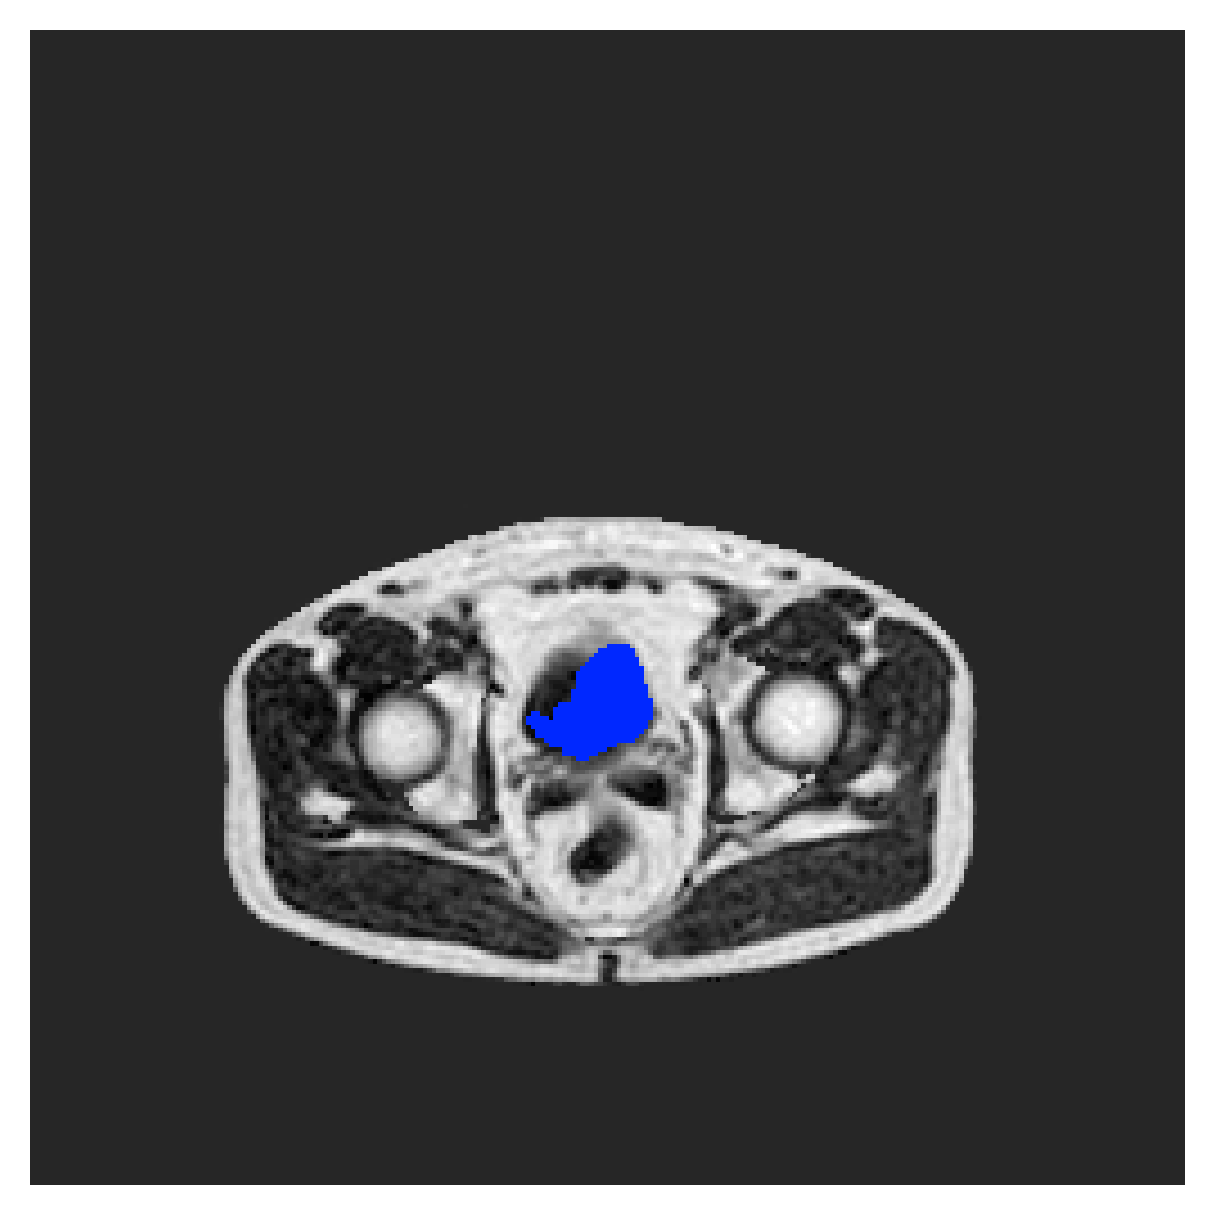

POEM

The Prospective investigation of Obesity, ENergy production and Metabolism (POEM) is a local (not currently publicly available; PI: L. Lind, see [22] for details) cohort of whole-body fat/water separated MR images. Full annotations of the liver, kidneys, bladder, pancreas and spleen are available for 50 subjects, providing a challenging segmentation dataset with heavily imbalanced classes of varying shapes. The resolution of the data is anisotropic, with reconstructed voxel size of in left-right, anterior-posterior and foot-head directions, respectively. For additional technical details regarding the acquisition and specifications of the images see [22].

The images contain two channels, one for water and one for fat content. For training, we normalize the volumes (per channel) and use 2D slices in the coronal plane, sized . The weak annotations are created synthetically, following the same procedure as described for the ACDC dataset.

5.2 Abdominal organ segmentation

Using 2D distance maps

In Table 3, the average DSC and HD95 results are shown (both using 2D and 3D distance maps) for the task of abdominal organ segmentation in POEM data (for boxplots see figures 8 and 9). We see that training with and (with distances calculated on 2D slices) performs comparably, while using and produces lower scores in both DSC and HD95 metric. On this dataset, the CRF-loss is able to compete with the boundary loss-based training strategies, even outperforming them on most classes. Most notably, all models trained with boundary loss appear to have a hard time segmenting the liver. We hypothesize this may be due to extremely severe class imbalance, as the liver covers a very large area compared to the rest of the classes. It is thus also more strongly affected by undersegmentations.

5.2.1 Qualitative comparison

In Figure 11 and 12 we show the same random slices in cases of calculating the boundary loss on 2D- and 3D-based distances, respectively. Comparing the two figures again indicates that the intensity-aware distances offer most improvement when calculated in 3D over 2D. The exception here is the MBD, which seems to even slightly degrade for most classes.